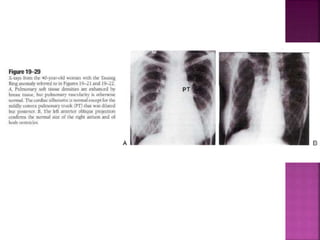

 CXR in DORV sub Ao VSD low PVR similar to

non restrictive peri mem VSD with high Qp

 Thymus is present in DORV TGA end of spectrum

unlike D-TGA wherein thymus typically absent

 Pulmonary trunk prominent (side by side

arteries)

 LA LV prominent in volume overload

 RA RV prominent with CCF

 Lung fields oligemic before fall in neonatal PVR

and with onset of pulmonary vascular disease

(semblance with non res VSD with EISENMENGER)